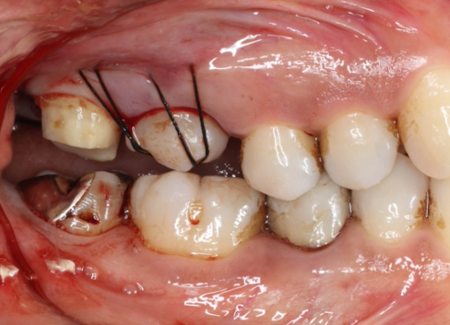

| STEP1 ドナー歯の抜歯 | STEP2 歯の移植及び縫合にて固定 |

|---|---|

![]() |